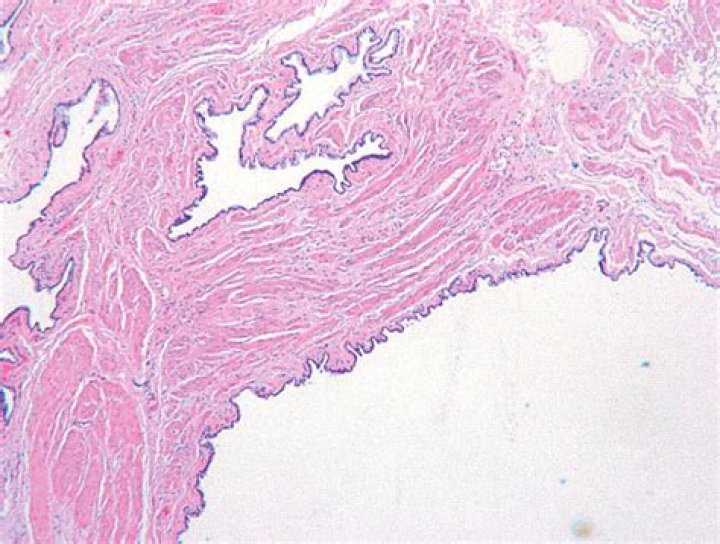

What does a Gartner duct cyst look like?

Gartner’s duct cystGross pathology of Gartner’s duct cystSpecialtyGynecology